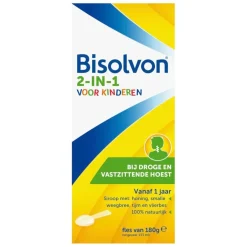

Gerelateerde producten

- Luchtwegen